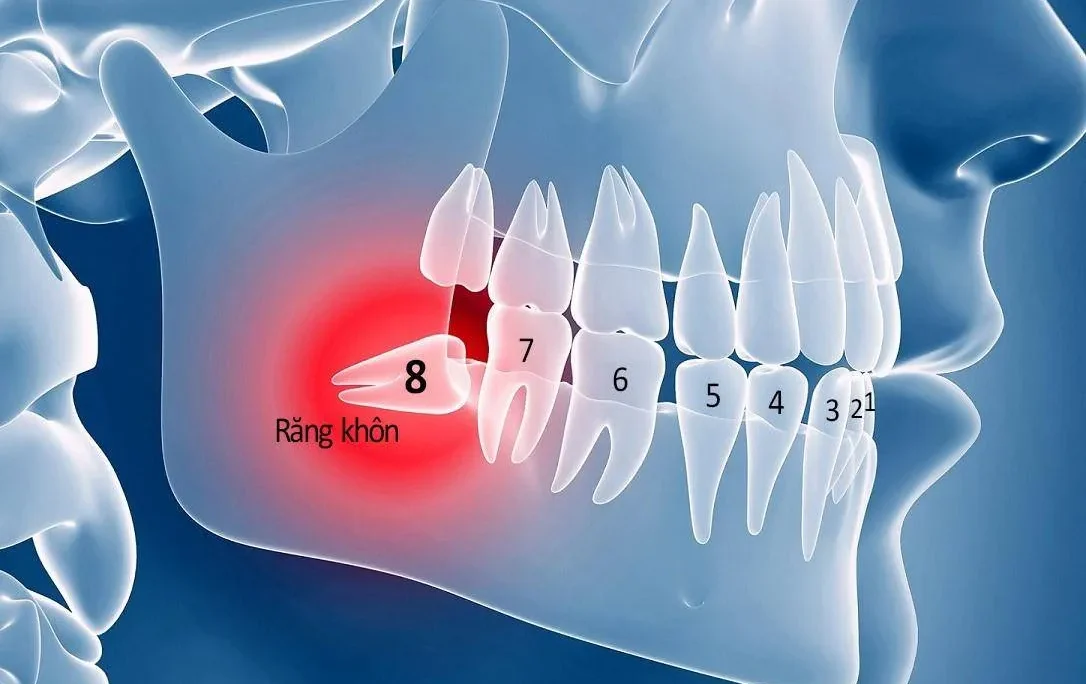

Tình trạng cứng khớp của răng

Nha sĩ sẽ kiểm tra răng có bị cứng khớp không bằng cách sử dụng dụng cụ chuyên dụng để gõ nhẹ lên răng. Nếu phát ra âm thanh rắn, vang, có thể răng đã bị ảnh hưởng khoảng 20% chân răng. Việc này có thể ảnh hưởng đến khả năng niềng răn. Do đó bác sĩ sẽ kiểm tra kỹ các yếu tố như đường viền nướu, cạnh cắn, mặt nhai. Đồng thời sử dụng x-quang để đánh giá tình trạng dây chằng nha chu. Nếu răng cứng khớp, quá trình niềng răng sẽ phức tạp hơn. Lúc này bác sĩ sẽ giải thích kỹ lưỡng cho bạn.

Giới hạn di chuyển của răng

Trong trường hợp bệnh nhân có tình trạng hô, móm nặng, nha sĩ sẽ cân nhắc kỹ khả năng niềng răng. Bác sĩ sẽ tính toán mức độ di chuyển tối đa của răng. Đồng thời xem xét liệu việc niềng răng có gây ảnh hưởng đến chân răng không. Nếu việc dịch chuyển răng có thể dẫn đến tiêu chân răng hoặc bật cùi răng khỏi xương, bác sĩ sẽ không khuyến khích tiến hành niềng răng.